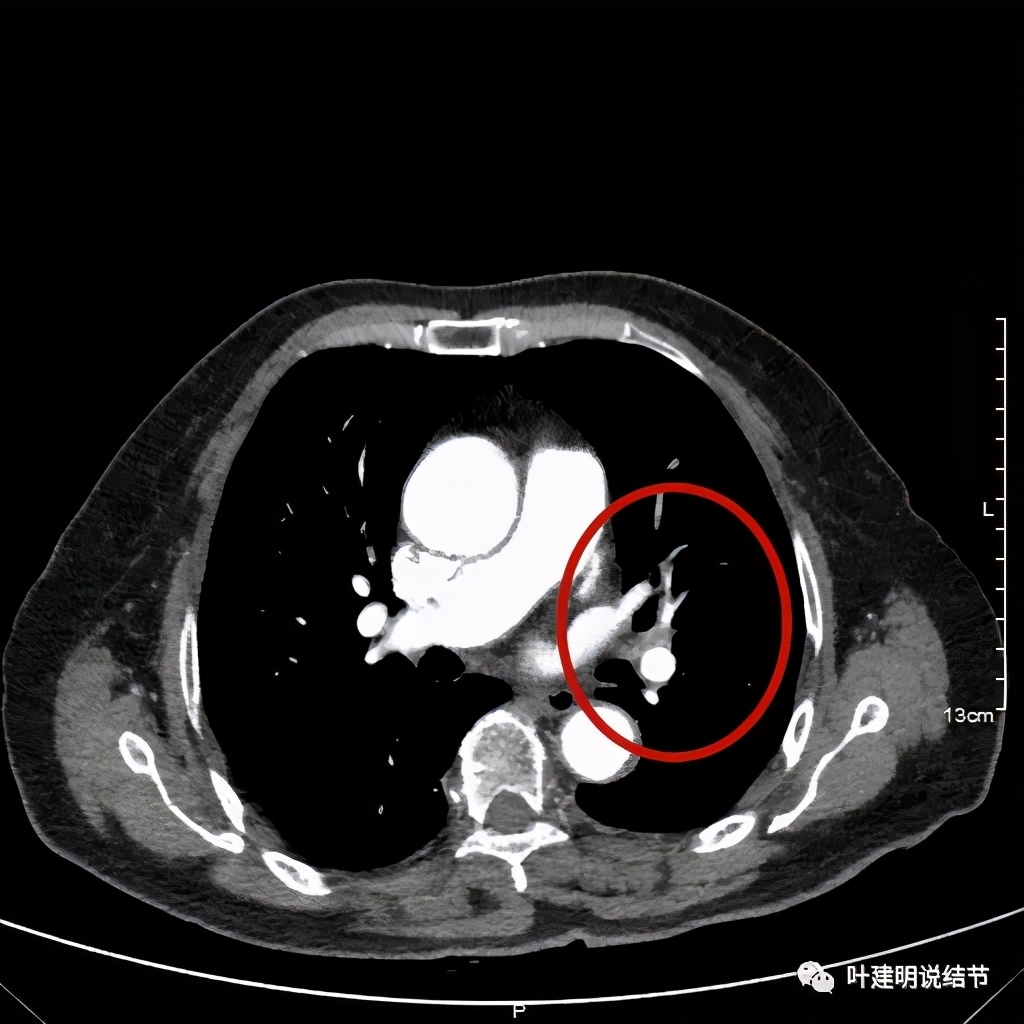

肺窗见原左上叶巨大占位已经明显缩小,甚至几乎不见了!而且上图示左上叶支气管清晰可见,内壁变光滑。纵隔窗增强又是如何的呢?

左上肺基本已经不见肿瘤,只在主动脉旁少许软组织影